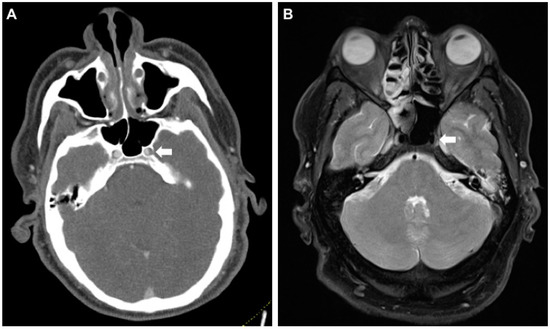

Figure 2. False-positive CT-A raising suspicion for an intramural hematoma of the left internal carotid artery (ICA) in its petrosal segment. (A) Axial CT-A of the skull base shows caliber asymmetry of the left ICA in the foramen carotideum (white arrow). (B) MR (proton-density fat saturated) rules out a wall hematoma. Asymmetry is presumably caused by the carotid plexus of nerves and sympathetics from the superior cervical ganglion (white arrow). MR, magnetic resonance.

Second, dedicated CT-A did not lead to more dissections revealed in our cohort but did elicit uncertain or suspicious cases requiring additional imaging (Figure 2).

Fifth, multimodal work-up of suspicious cases is highly relevant as with a dedicated head-and-neck CT-A a tendency toward false positives can be seen. With ultrasound, which often is used as the first add-on diagnostic due to fast availability and low cost, false negatives are very likely [12], being unable to safely rule out any CeAD and, as in our cases reported here, not being able to confirm CeAD either. Influence of dedicated training of ultrasound examiners or compulsory use of state-of-the-art techniques such as b-flow or contrast-enhanced ultrasound should be elaborated.